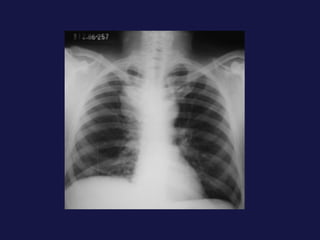

Carcinoma bronquioloalveolar  (1.5-6,5%) Subtipo de adenocarcinoma. Empieza como nódulo periférico, espiculado, hasta parecer una masa considerable, condensación alveolar o infiltrados múltiples 50% con cola pleural. Es FREC. el broncograma aéreo, puede presentar cavitación.